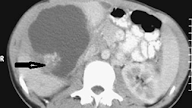

This is radiology images of Oriental cholangiohepatitis. Computed tomography reveals stones (arrows) within dilated intrahepatic bile ducts.

In some patients the sphincter of Oddi is destroyed, with reflux of gas and intestinal content into bile ducts. At times orally ingested contrast refluxes into the bile ducts. Stones and air bubbles can be confused with each other. Computed tomography can suggest the diagnosis by detecting dilated intrahepatic bile ducts and stones. Once the diagnosis is suspected, ERC defines the underlying anatomy using, if necessary, a balloon catheter to dilate and obtain adequate filling of intrahepatic ducts. At times percutaneous cholangiography is necessary to outline the full extent of hepatolithiasis.